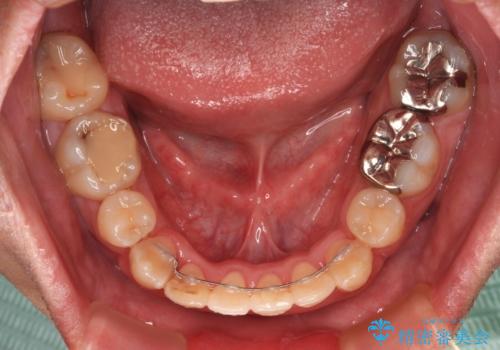

- 上下の八重歯やデコボコを気にして来院された患者様です。

上下ともに八重歯が顕著であったので、上下左右第一小臼歯4本を抜歯し、ワイヤー装置にて矯正治療を行うこととしました。

デコボコが強いことが原因で歯間部に汚れが溜まりやすい状態でしたが、矯正前にできる限り汚れが少なくなるようにブラッシングなどの指導を行い、口腔状態が改善された後にワイヤー装置を装着することとしました。